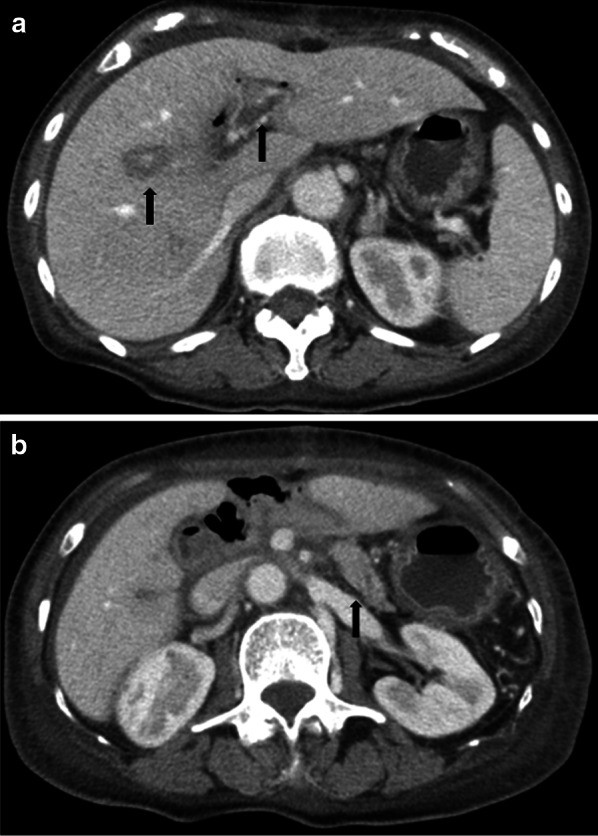

Fig. 1.

a Contrast-enhanced computed tomography (CECT) scan showing a hypovascular tumor abutting the superior mesenteric artery (SMA) and involving < 180° of the circumference of the artery without encasement. b Intraoperative photographs. The black arrowhead shows the anastomosis of the superior mesenteric vein with the 1st jejunal vein. SMA: superior mesenteric artery. SMV: superior mesenteric vein. 1st JJV: 1st jejunal vein. PV: portal vein. MCA: middle colic artery. MCV: middle colic vein. IMV: inferior mesenteric vein. SV: splenic vein. LGV: left gastric vein. IVC: inferior vena cava